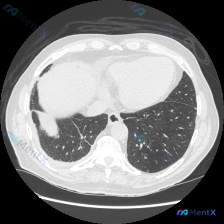

看到一个胸部CT病例(肺窗、横断面,心室水平),整理了一下思路。 病例资料: - 双侧胸廓对称,纵隔居中,双肺透亮度基本正常 - 右肺中叶/下叶外侧段可见类圆形实性结节/肿块影 - 病灶边缘相对清晰,部分区域呈轻度浅分叶状,密度较均匀,无钙化或空洞 - 病灶周围肺纹理走行正常,无明显胸膜牵拉、星芒状...

整理了一个很有讨论价值的影像病例,核心是避免对单张CT的过度解读。 先看影像发现(核心事实) - 扫描层面:胸部中下段肺窗,图像质量尚可 - 关键病灶:右肺中叶/下叶背段邻近区域,一枚类圆形实性结节 - 阳性征象:边界清晰,可见浅分叶征,有血管集束征(血管向结节汇聚) - 阴性征象:无明显毛刺征,无...